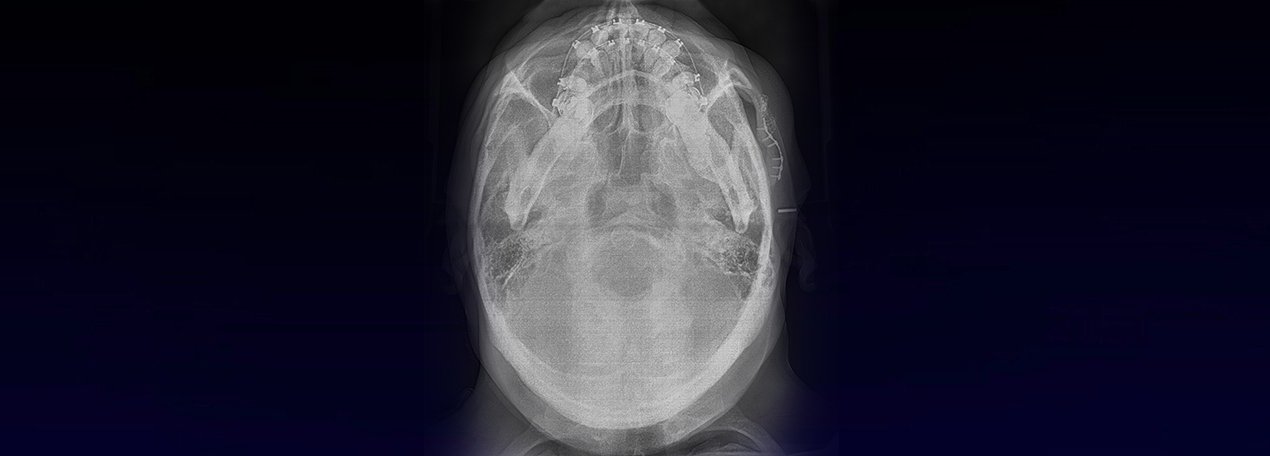

A la evaluación de las radiografías Panorámica, Waters, y radiografía Periapical, observamos, neumatización alveolar y opacificación parcial de seno maxilar izquierdo, lecho alveolar de correspondiente a pieza 2.6, con discontinuidad de la cortical de la pared basal de seno maxilar adyacente, y engrosamiento de la membrana antral de seno maxilar ipsilateral. Signos radiográficos compatibles con proceso inflamatorio sinusal (Sinusitis) en relación a comunicación buco sinusal.